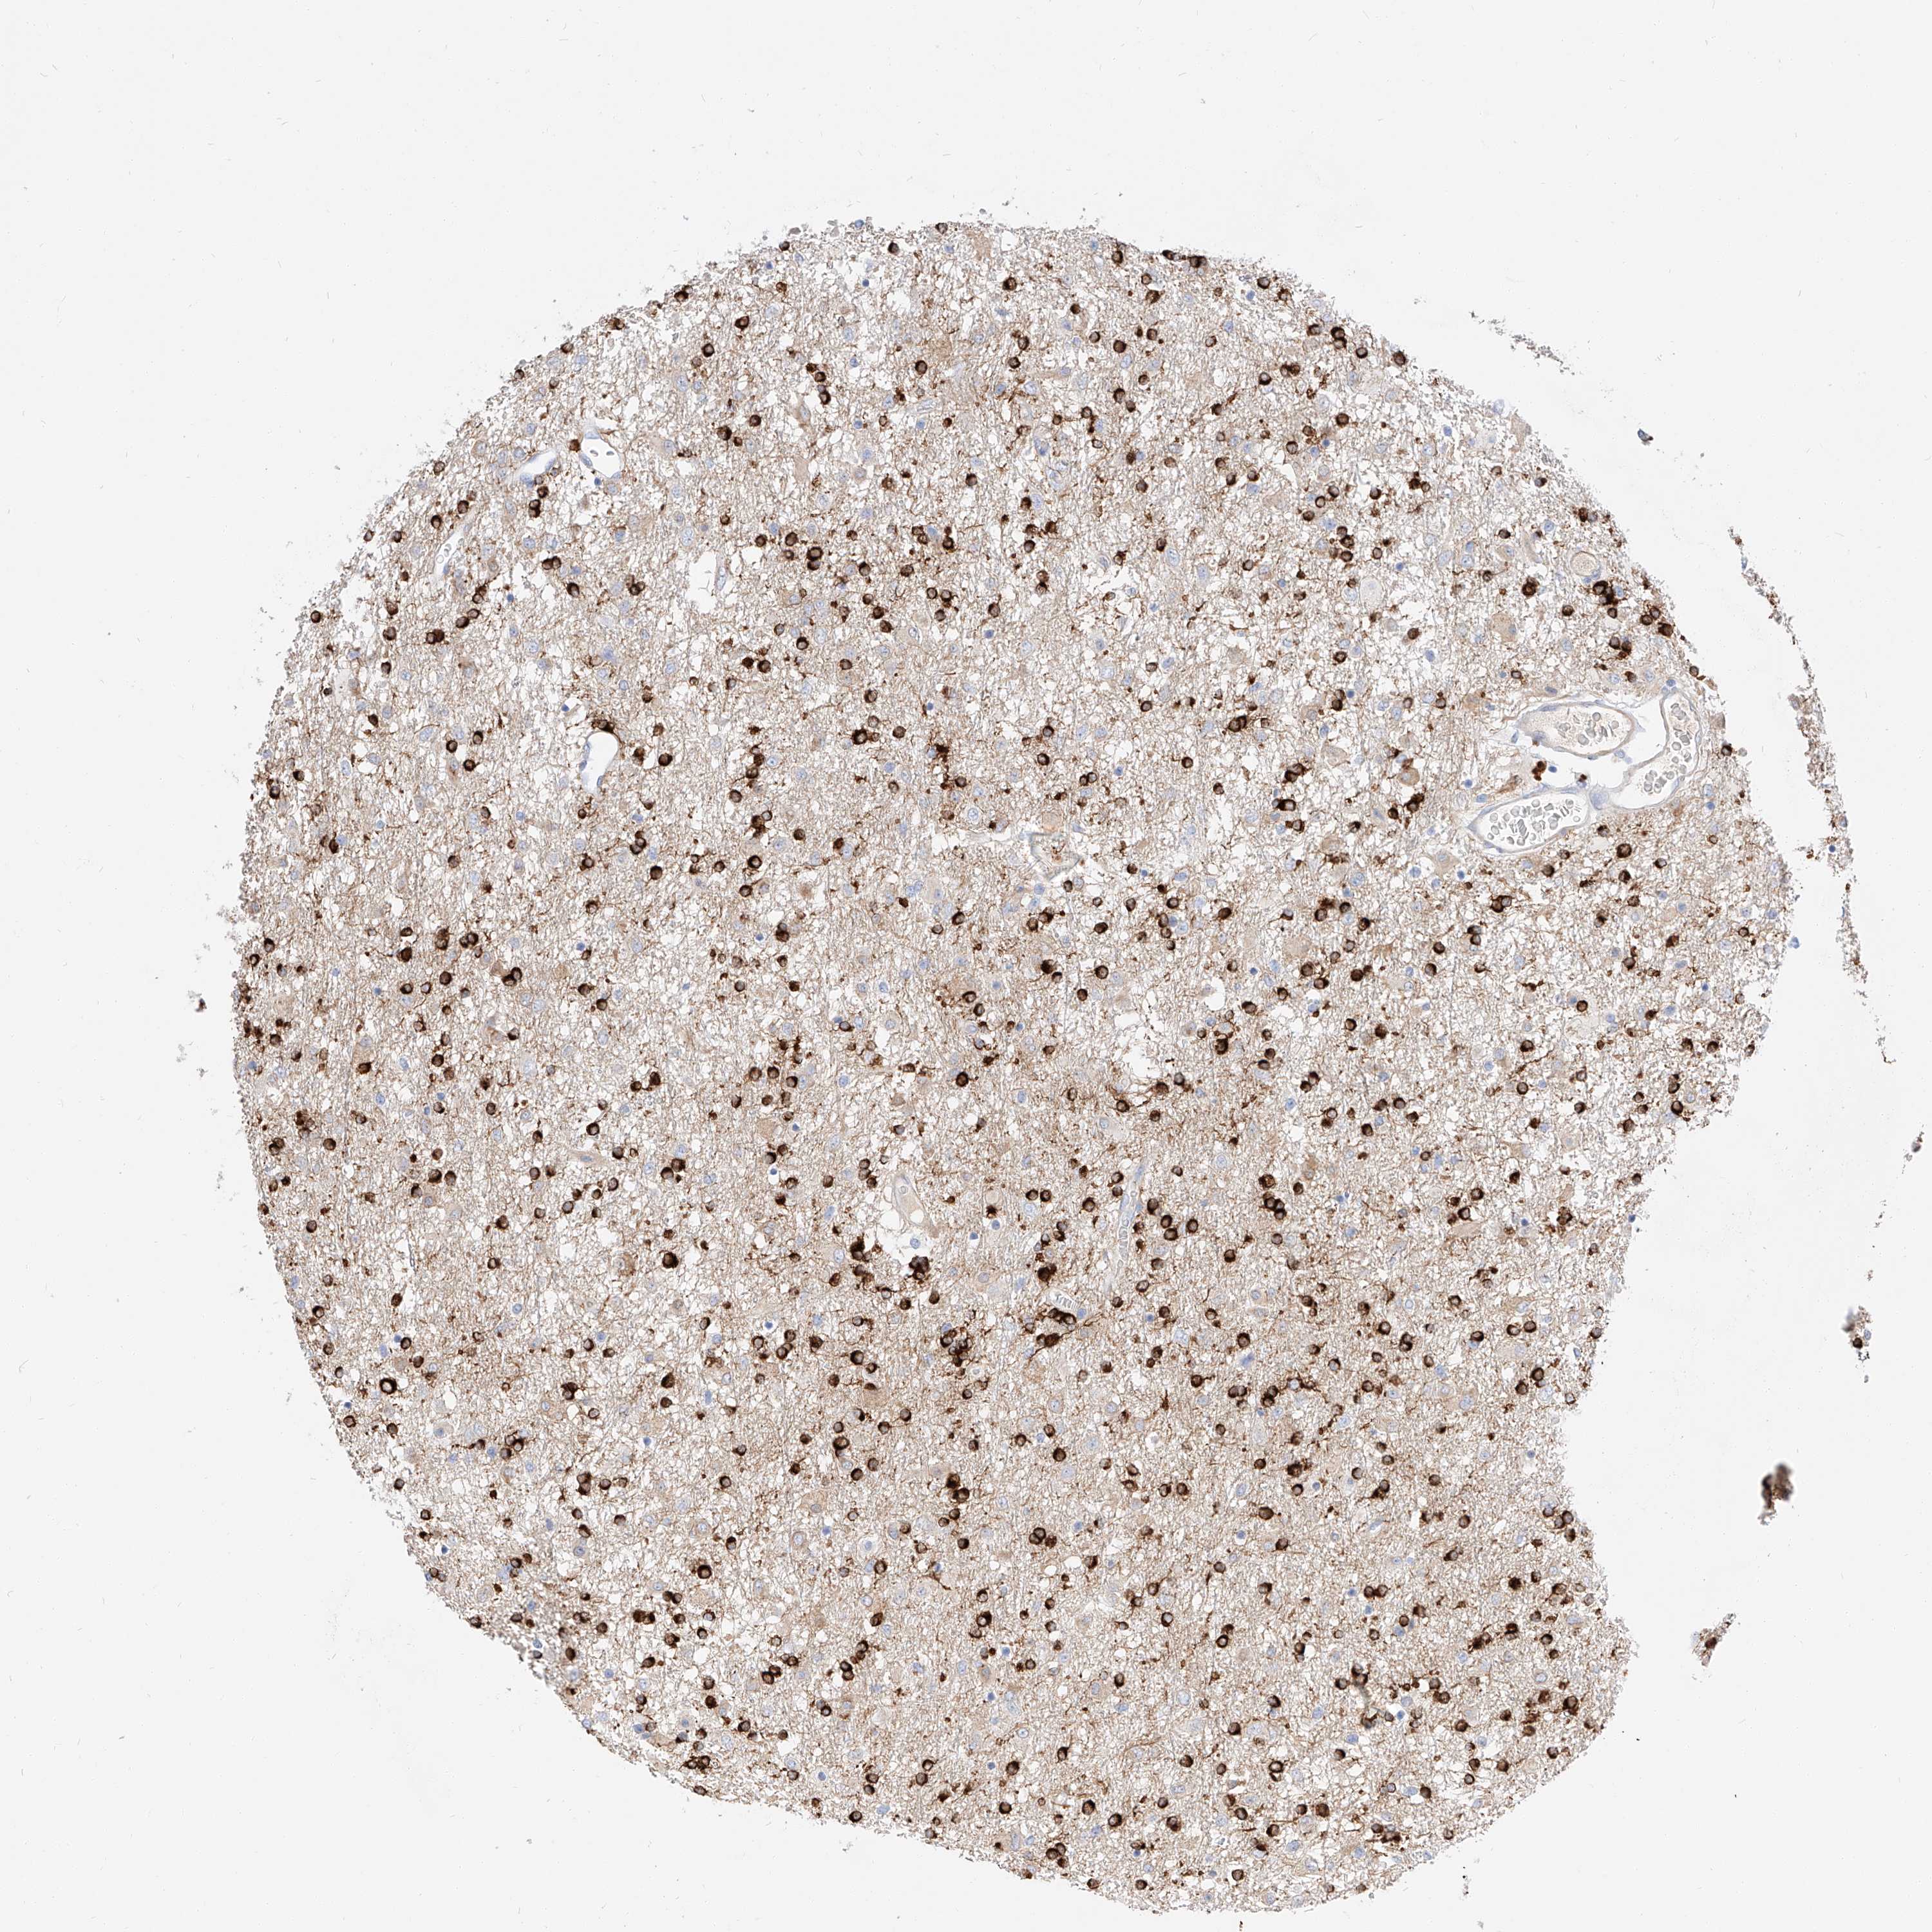

GLIOMA - Protein expressioni

A mouse-over function shows sample information and annotation data. Click on an image to view it in a full screen mode. Samples can be filtered based on level of antibody staining by selecting one or several of the following categories: high, medium, low and not detected. The assay and annotation is described here.

Note that samples used for immunohistochemistry by the Human Protein Atlas do not correspond to samples in the TCGA dataset.

Antibody stainingi

Antibody staining in the annotated cell types in the current human tissue is reported as not detected, low, medium, or high, based on conventional immunohistochemistry profiling in selected tissues. This score is based on the combination of the staining intensity and fraction of stained cells.

Each image is clickable and will lead to virtual microscopy that enables deeper exploration of all samples and also displays staining intensity scores, fraction scores and subcellular localization as well as patient and tissue information for each sample.

Antibody HPA029712

Antibody HPA029713

Staining

High

Medium

Low

Not detected

Intensity

Strong

Moderate

Weak

Negative

Quantity

>75%

75%-25%

<25%

None

Location

Nuclear

Cytoplasmic/membranous

Cytoplasmic/membranous,nuclear

Glioma, malignant, High grade

Glioma, malignant, Low grade

Glioblastoma, NOS